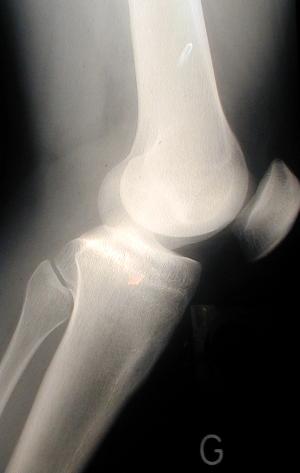

6- articulation : De quelle articulation s'agit-il ?

un coude un genou un cou